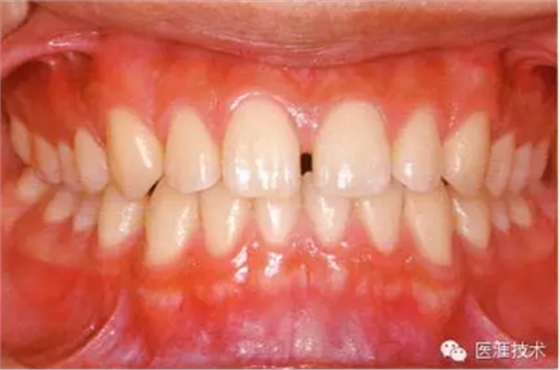

18歲男性的健康口腔內(nèi)部

圖為18歲男性,無特殊全身疾病,不抽煙。持續(xù)保養(yǎng)10年。牙菌斑控制比以前好,因刷牙稍稍過度臉頰側(cè)有牙齦萎縮傾向,但牙齒及牙周組織仍保健康。